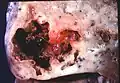

Pathology image of a lung abscess. -